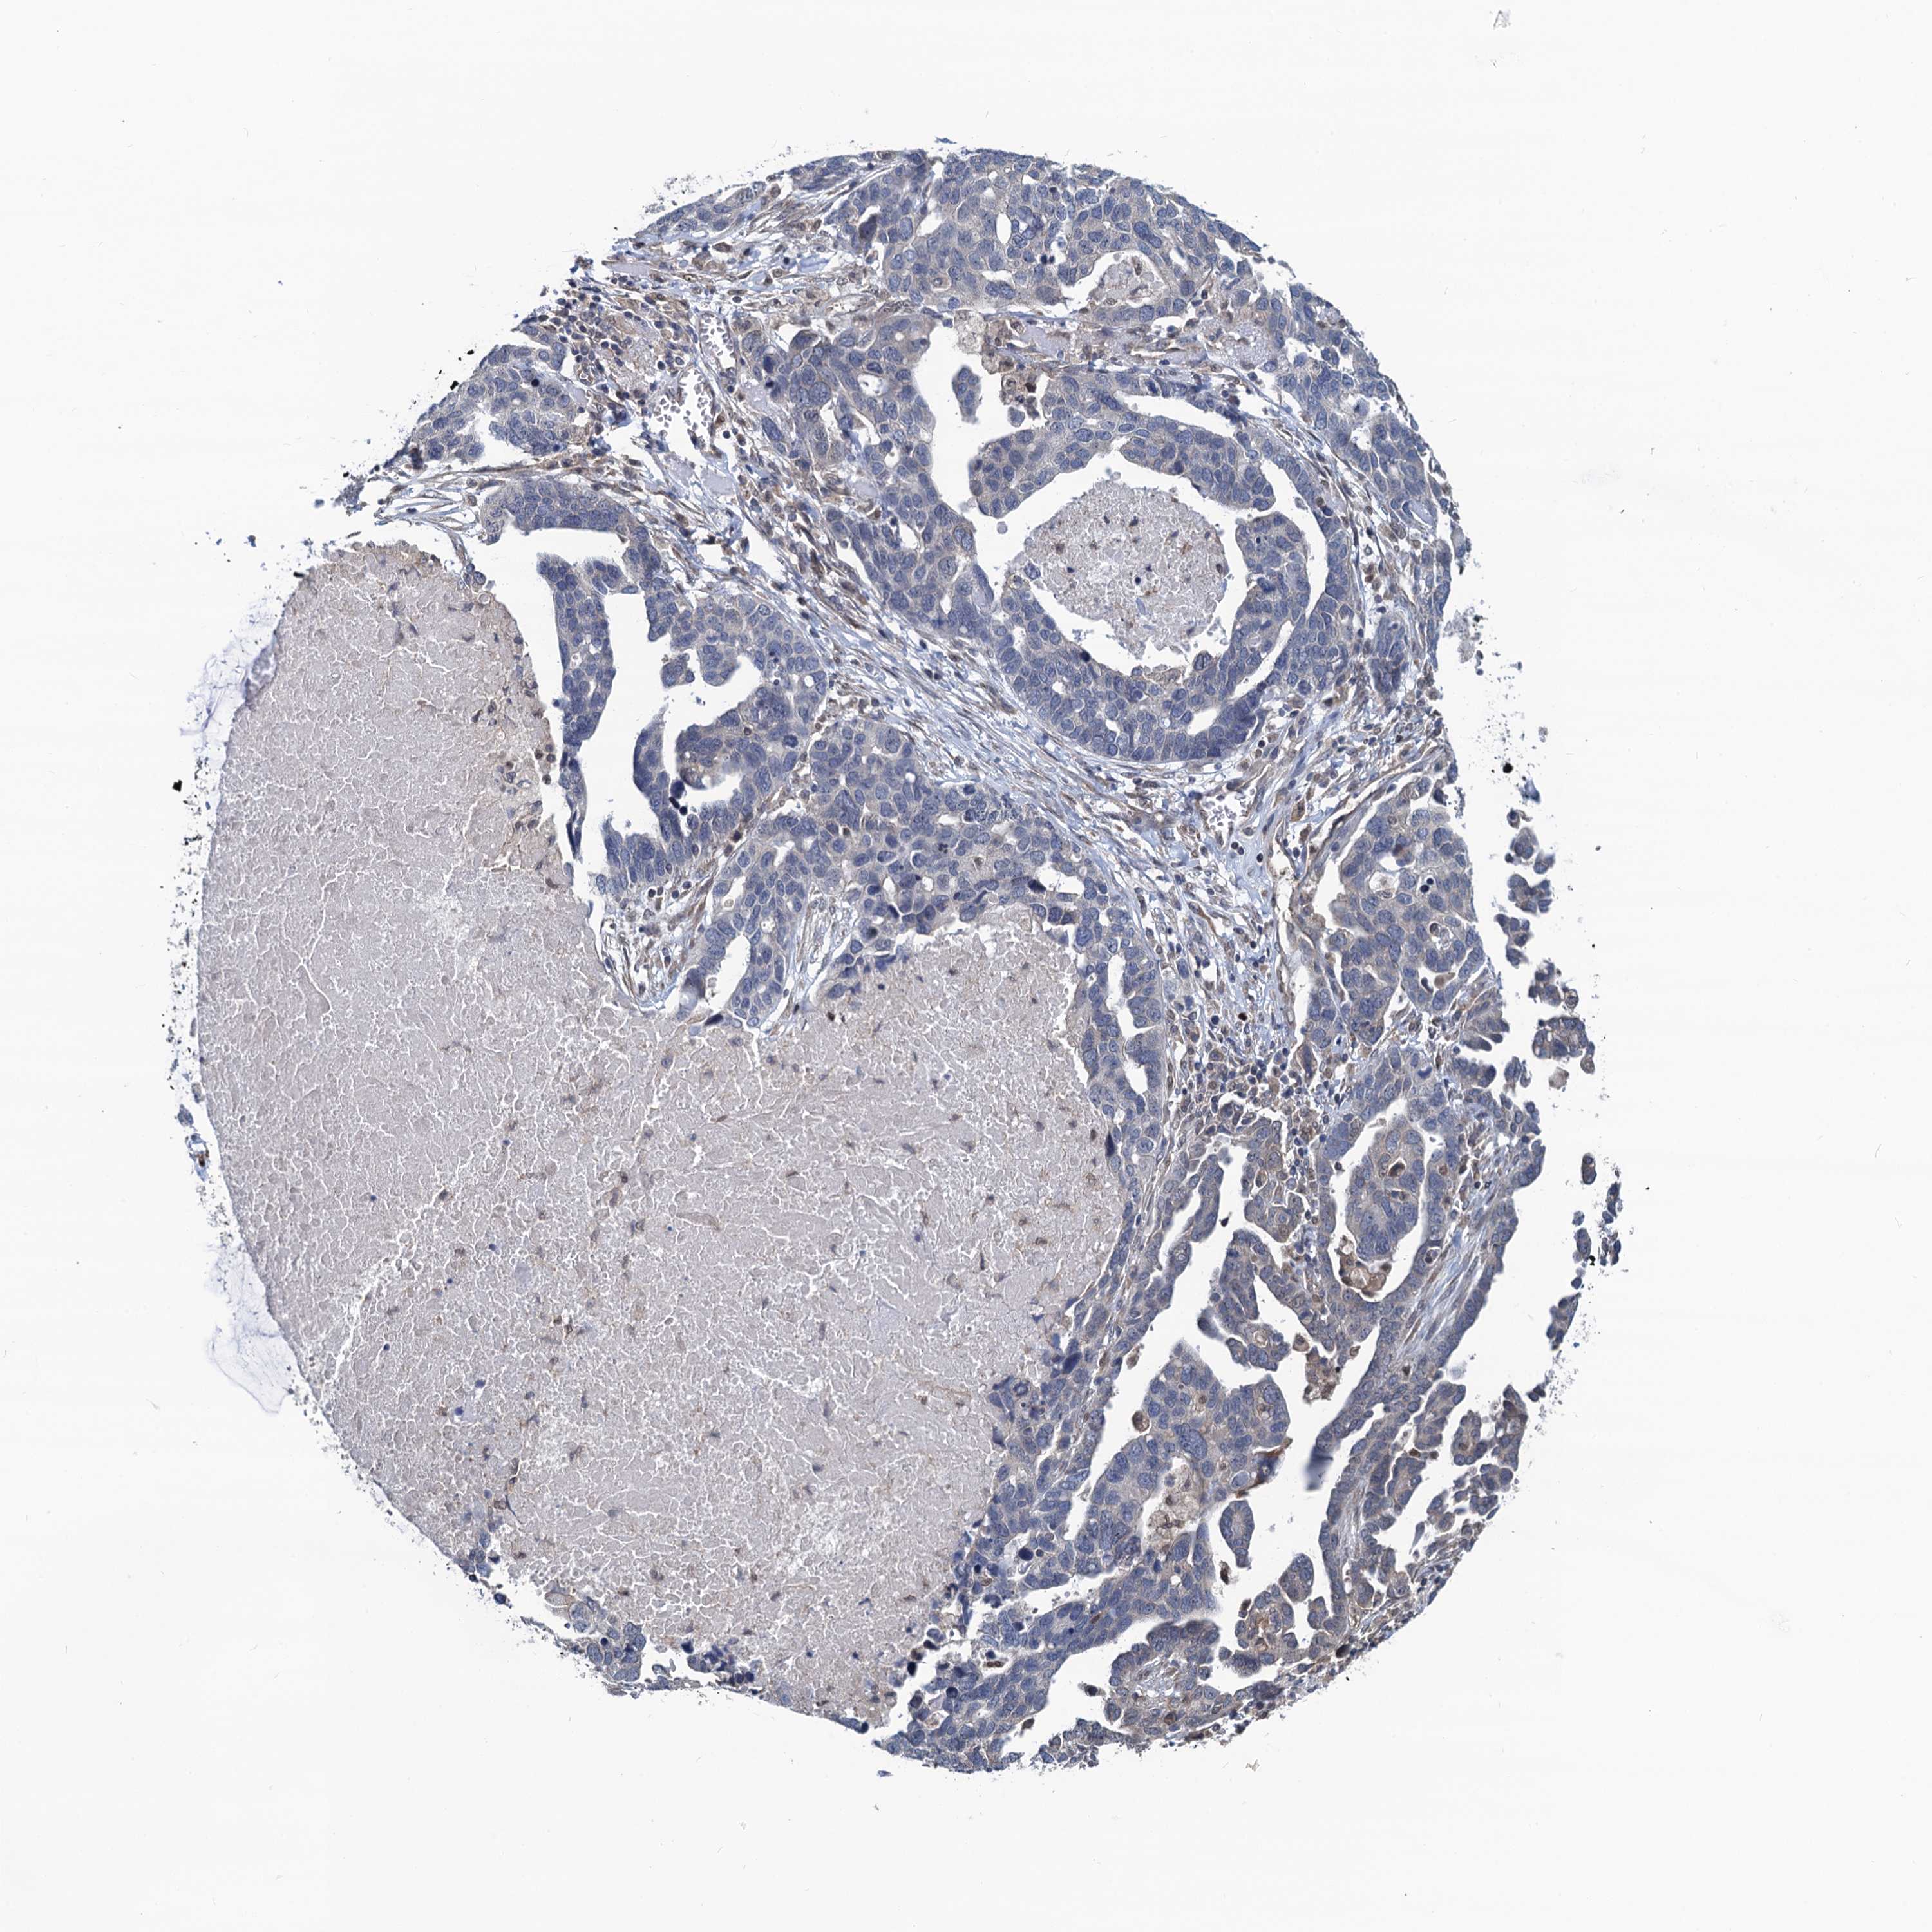

OVARIAN CANCER - Protein expressioni

A mouse-over function shows sample information and annotation data. Click on an image to view it in a full screen mode. Samples can be filtered based on level of antibody staining by selecting one or several of the following categories: high, medium, low and not detected. The assay and annotation is described here.

Note that samples used for immunohistochemistry by the Human Protein Atlas do not correspond to samples in the TCGA dataset.

Antibody stainingi

Antibody staining in the annotated cell types in the current human tissue is reported as not detected, low, medium, or high, based on conventional immunohistochemistry profiling in selected tissues. This score is based on the combination of the staining intensity and fraction of stained cells.

Each image is clickable and will lead to virtual microscopy that enables deeper exploration of all samples and also displays staining intensity scores, fraction scores and subcellular localization as well as patient and tissue information for each sample.

Antibody HPA041514

Staining

High

Medium

Low

Not detected

Intensity

Strong

Moderate

Weak

Negative

Quantity

>75%

75%-25%

<25%

None

Location

Nuclear

Cytoplasmic/membranous

Cytoplasmic/membranous,nuclear

Cystadenocarcinoma, serous, NOS

Carcinoma, endometroid

Cystadenocarcinoma, mucinous, NOS

Carcinoma, NOS